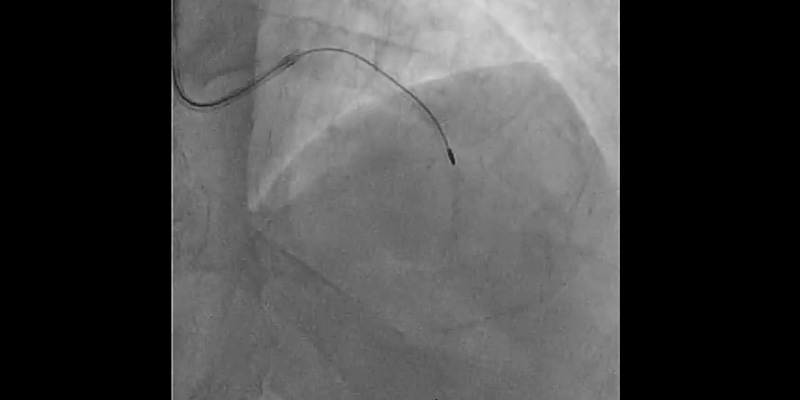

• The LAD was first wired with a hydrophilic wire and then exchanged for the Rotawire™ Extra Support guide wire using a microcatheter.

• Rotational atherectomy with a 1.25mm burr: A 1.25 mm burr was selected due to the severity of the stenosis and calcium. Individual rotablation runs (30-45 sec) were done with a burr speed of 165,000 rpm

• Due to severe calcification and vessel angulation, the burr jumped distal to the lesion even with a gentle manipulation of the system. Withdrawal of the burr was unsuccessful. The system was put into Dynaglide which also resulted in an unsuccessful retrieval attempt. A hydrophilic guidewire was placed parallel to the RotablatorTM catheter but a balloon could not pass through the 7Fr femoral guiding catheter.